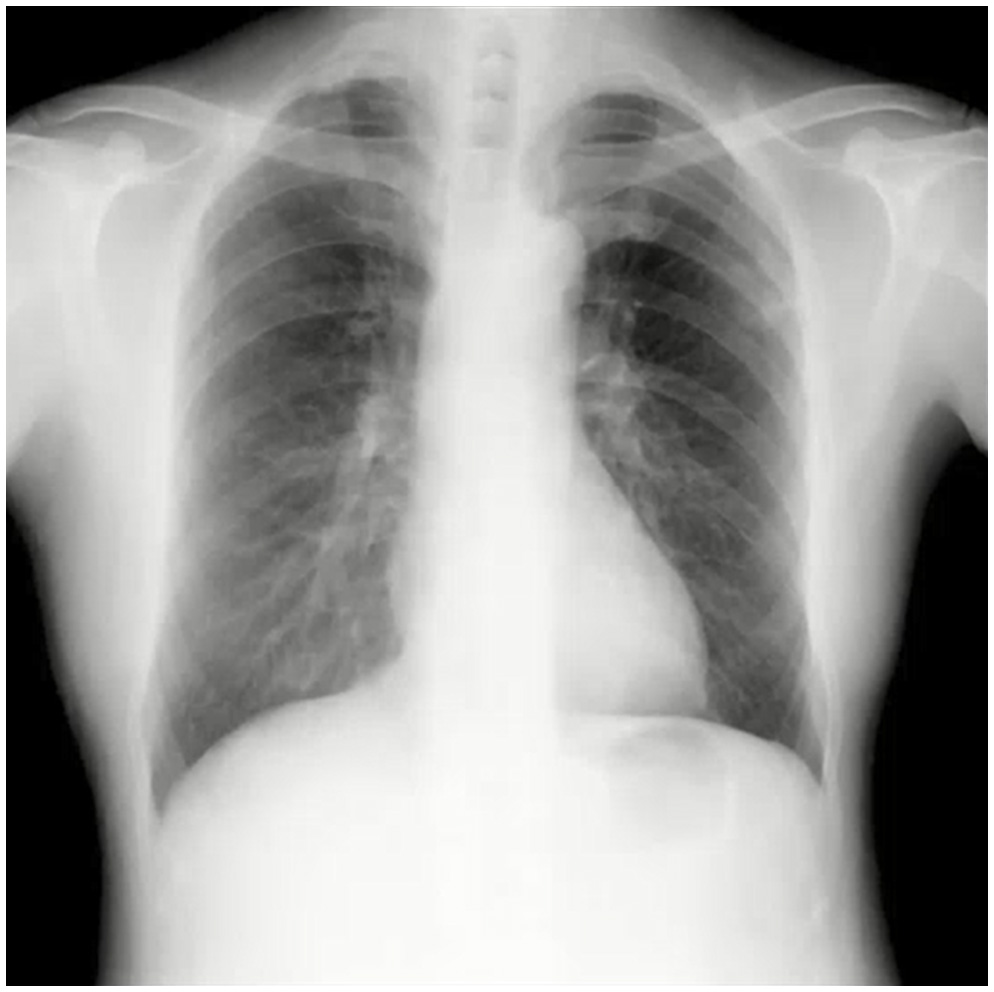

デジタルX線動画撮影システム(Dynamic Digital Radiography)は従来の単純X線撮影と同様に、一般X線撮影装置を用いて簡便に撮影できる新たな検査法であり、回診用X線撮影装置「AeroDR TX m01」によりベッドサイドでのX線動画撮影が可能となり、更なる広がりを見せています。